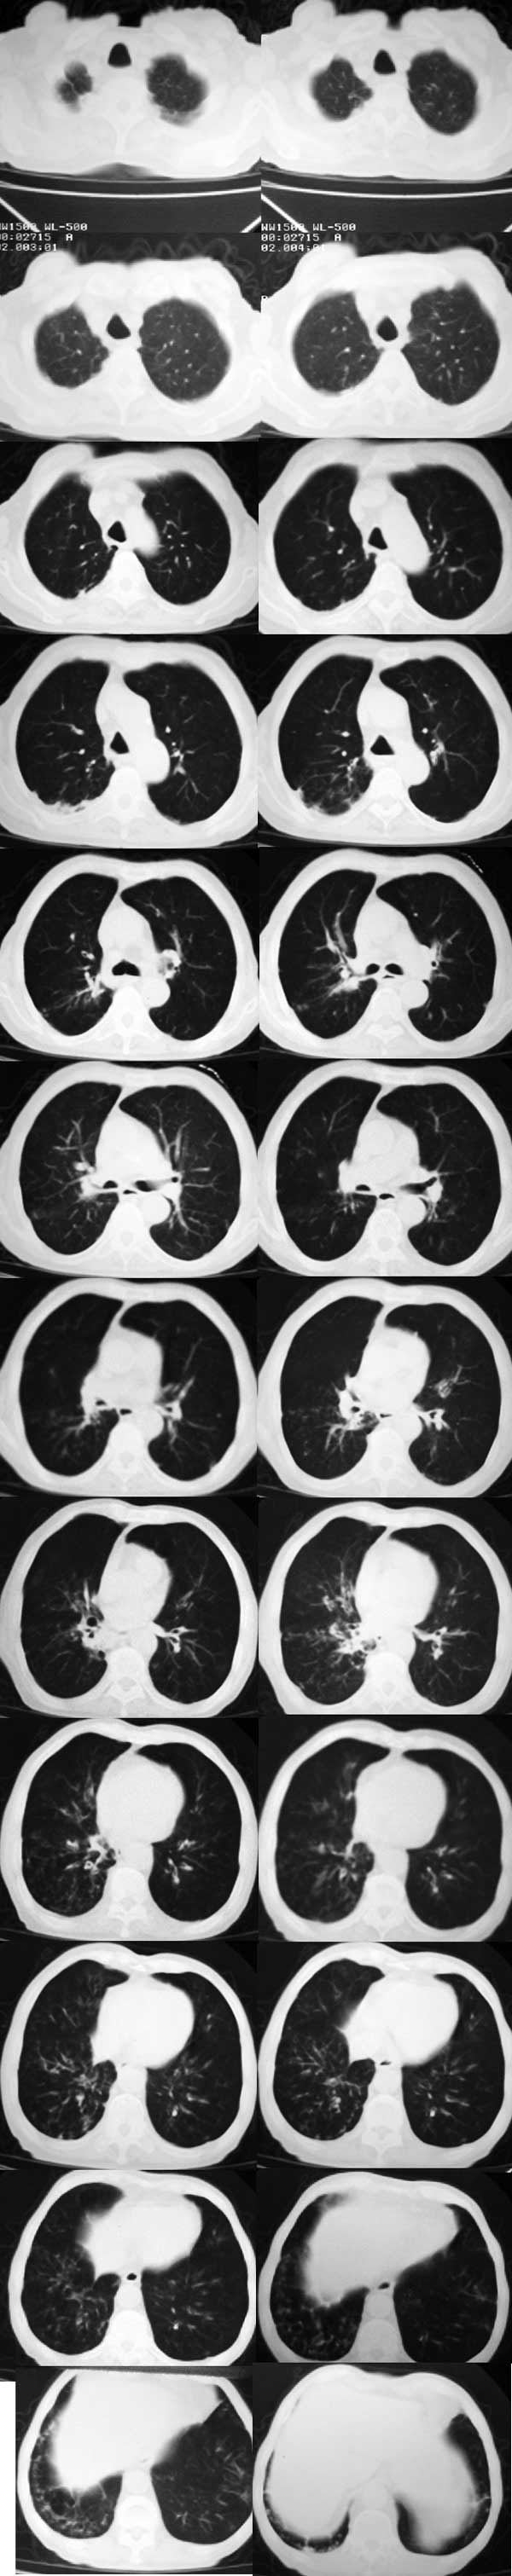

男 83  咳嗽 吐大量白色泡沫样痰 低热 间断性消炎治疗3-4个月

右中下肺及上叶后段可见肺纹理增粗,支气管血管束增粗,支气管分支可见轻度扩张,间杂有斑片状高密度影,可见“树芽征”,右侧肺门区似见胸膜粘连,纵隔内未见明显肿大淋巴结影。综上所见,应该首先考虑慢性支气管疾患并细支气管炎症,建议根据痰培养和药敏试验合理用药,红霉素对细支气管炎的治疗应为首选。

双肺体积增大,透亮度增高,肺纹理稀疏。右肺中叶及下叶散在小片絮状稍高密度影。右肺下叶各段及细支气管均可见轻度扩张,且管壁增厚。右侧肋胸膜局限性增厚,形态不规则。

考虑:1、右肺中叶、下叶间质性炎性改变。

2、右侧局限性胸膜炎。

3、慢性支气管炎、肺气肿。